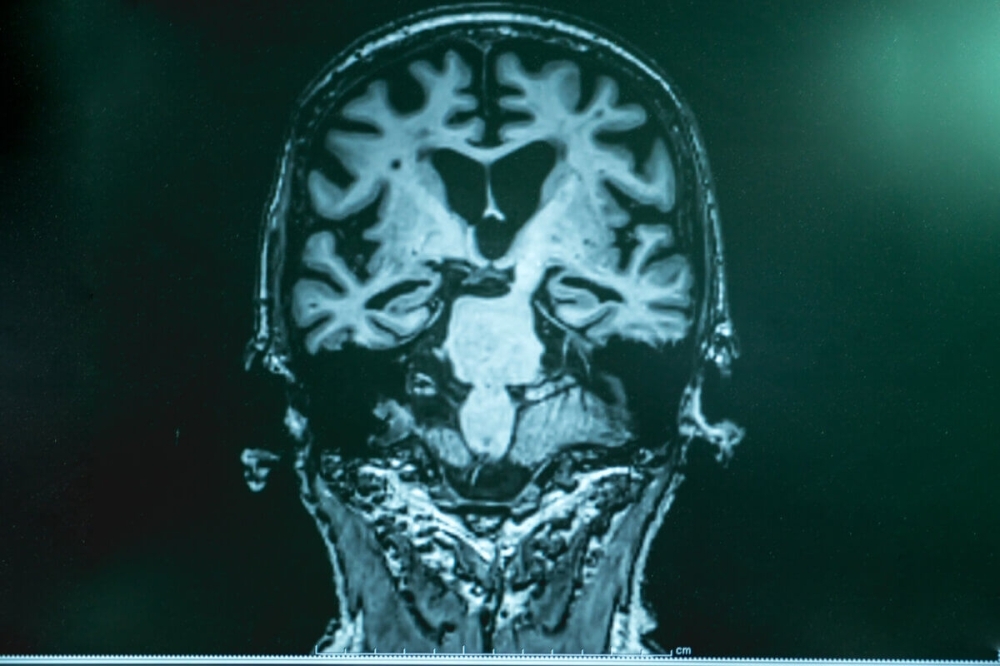

يعتقد كثيرون أن الزهايمر يبدأ بمشكلات الذاكرة، لكن الأبحاث الحديثة تكشف أن فقدان حاسة الشم قد يكون الإنذار الأول قبل سنوات من ظهور الأعراض الإدراكية. دراسة جديدة نُشرت في Nature Communications أوضحت أن الخلايا المناعية في الدماغ، المعروفة بـ«الخلايا الدبقية الدقيقة»، تهاجم الألياف العصبية المسؤولة عن معالجة الروائح، مما يؤدي إلى تدهورها في مراحل مبكرة جدًا من المرض.

اعتمد الباحثون على نماذج فئران مصممة وراثيًا لتطوير أعراض شبيهة بالزهايمر. أظهرت النتائج أن الألياف العصبية في المصباح الشمي بدأت بالتدهور منذ الشهر الأول، حيث وصلت نسبة الفقد إلى: 14% عند عمر شهرين، 27% عند ثلاثة أشهر، و33% عند ستة أشهر. بينما بقيت مناطق أخرى مثل الحُصين والقشرة أمام الجبهية غير متأثرة في هذه المرحلة. المدهش أن الخلايا الدبقية لم تكتفِ بتنظيف الحطام، بل ابتلعت اتصالات عصبية حية، وهو ما سرع فقدان الشم.

في عينات بشرية بعد الوفاة، لوحظ انخفاض واضح في الألياف المنتجة للنورأدرينالين داخل المصباح الشمي لمرضى الزهايمر المبكر. أما في الأشخاص الأحياء، فقد أظهرت فحوصات TSPO-PET نشاطًا مرتفعًا للخلايا المناعية لدى المصابين بضعف إدراكي بسيط، وهو ما يرجح أن فقدان الشم يظهر قبل تدهور الذاكرة. إضافة إلى ذلك، سجل هؤلاء المرضى أداء أضعف في اختبارات تحديد الروائح مقارنة بالأصحاء.